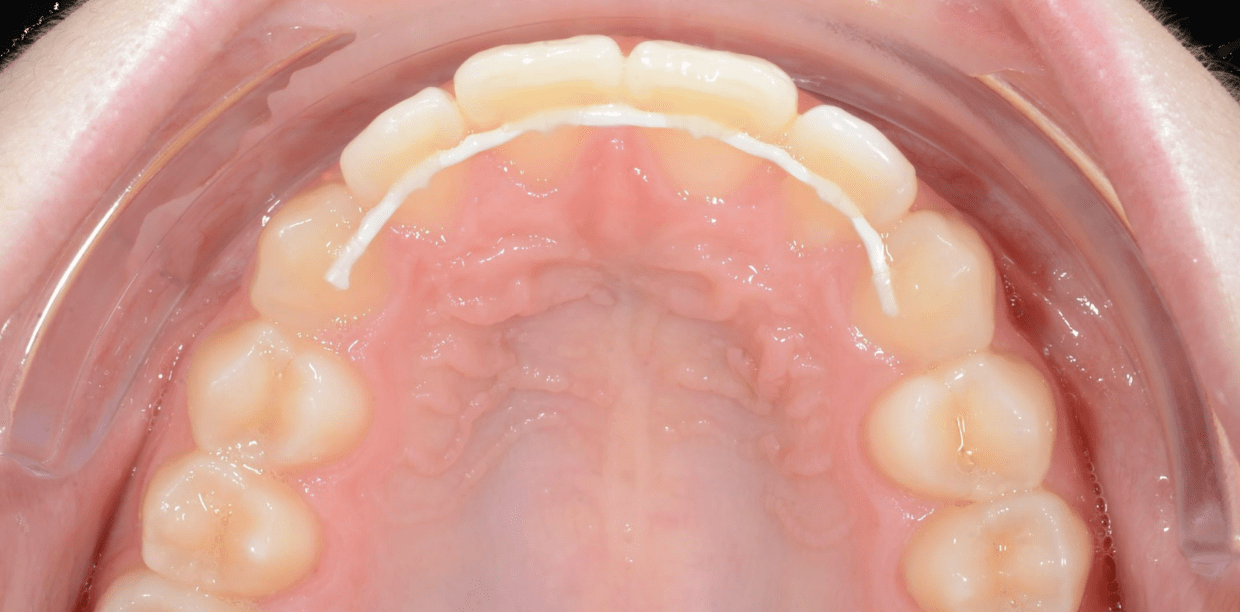

Cas cliniques

Simple - A2

Simple - A2

Simple - A2